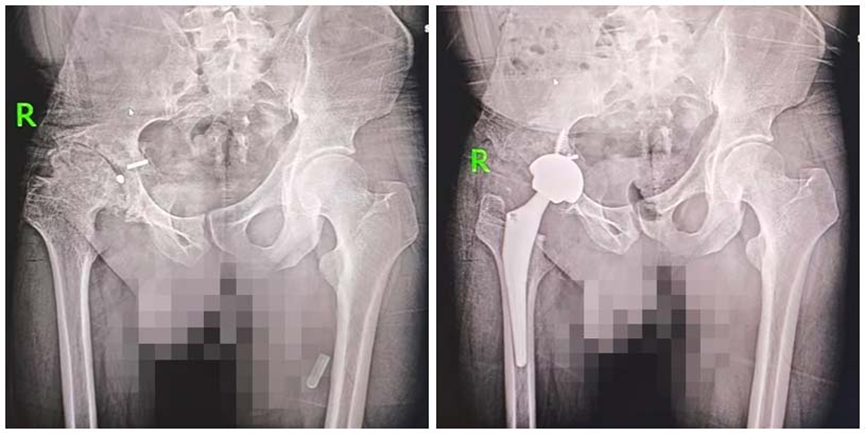

新疆小伙小张,今年刚满30岁,因小时候的一场车祸,他的髋部受到严重的外伤,走路呈现长短腿,跛行明显,为恢复正常行走步态,小张在父母的陪同下,从新疆跨越3400公里专程来到济南关节外科医院,成功进行了全髋关节置换手术,圆梦健康行走。

2025年,在多方打听后,张父知道了治疗髋关节疾病的专科医院——济南关节外科医院,随即带领全家人奔赴济南。入院后,专家团队为其进行了细致的检查,确诊其右侧股骨头坏死已至晚期,关节功能严重受损。结合患者病情与身体状况,专家团队制定了机器人辅助全髋关节置换手术方案,并联合骨科、内科、麻醉科等多科室进行术前会诊,完善手术预案,全力保障手术安全。

在多学科紧密协作下,手术顺利实施,通过骨科机器人的精准辅助,成功为小张置换了病变的股骨头。考虑到小张跛行病史长达20余年,患肢短缩畸形严重,术后康复挑战较大,医院康复团队为其量身定制了系统化康复方案,细化每日训练内容与康复目标,由康复医师、责任护士全程一对一指导,实时跟进恢复情况,及时调整训练计划。

经过20多天的规范治疗与专业康复,小张的患肢功能得到显著改善,右脚跟能够完全着地,双腿长度恢复均衡,走路步态基本与常人无异。看着彻底摆脱跛行、身姿挺拔的儿子,小张的父亲激动不已,连连称赞:“你们的手术做的太好了,服务贴心,这趟来得太值了!”